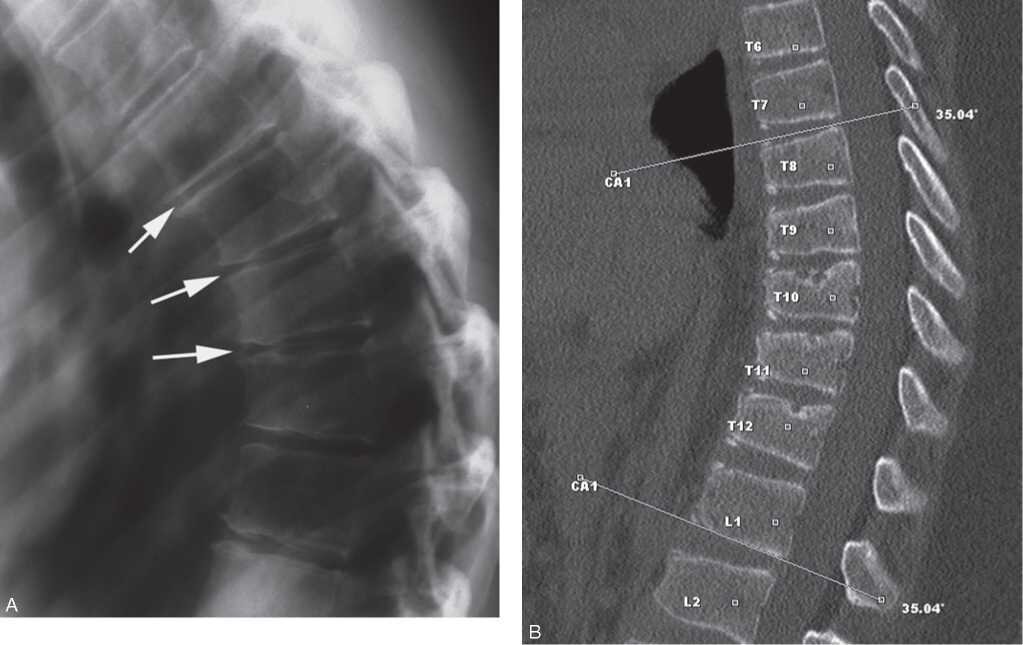

При принятии окончательного решения о степени годности к службе председатель медицинской комиссии руководствуется 66 статьей «Кифоз позвоночника с деформацией 3 и более позвонков». Поэтому вы должны предоставить максимум документальных доказательств и справок, что есть данная проблема.

• снимок грудного отдела позвоночника (желательно в нескольких проекциях);

• заключение о количестве и степени повреждения позвонков;